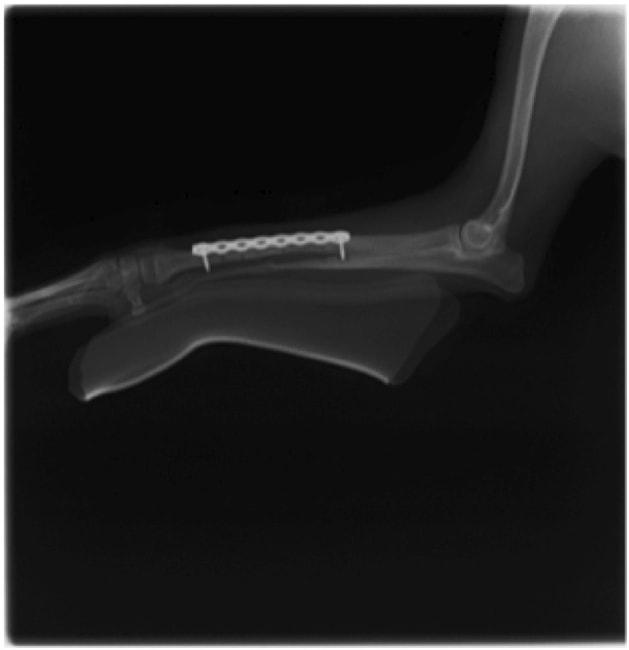

トイプードル 右遠位橈尺骨短斜骨折のALPSによる内固定